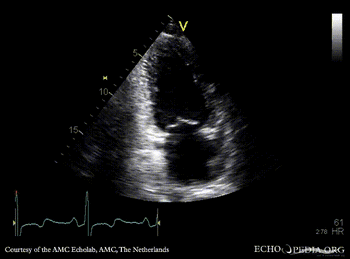

Case 159